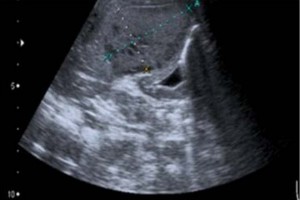

Diplomados en Ultrasonografía

Hola, conoce nuestros diplomados.